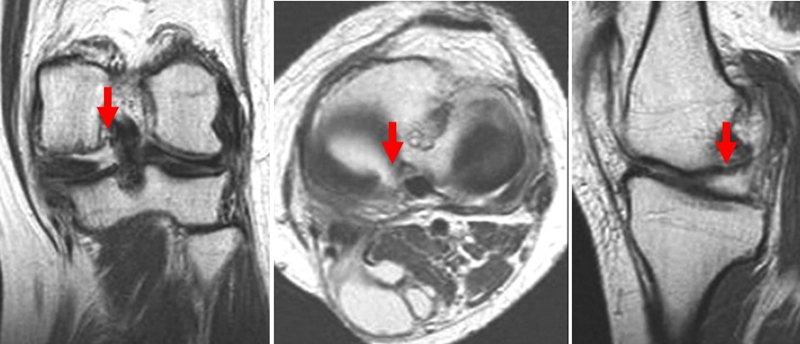

SONK与内侧半月板突出的相关研究中,100%(104)SONK中都有半月板突出,4个SONK在发病前因膝关节疼痛体检发现半月板突出,几个月后通过MRI检查显示存在 SONK。

研究证明半月板挤压是SONK的发病机制之一,半月板挤压的进展可能与SONK的发展有关。